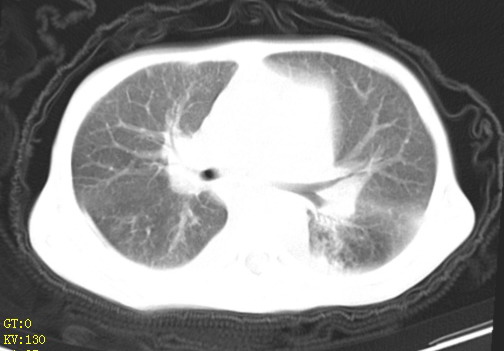

女,12岁,气促、咳嗽2天,3个月前查胸片示:两肺感染,急诊入院查ct,血常规等未检查。

1、左心房、左心室增大,考虑左心衰, 2、肺水肿合并感染 3、双侧胸腔积液

双肺中下野不规则片絮状阴影,中外带明显,双侧胸腔少量积液,心影增大,心腔密度减低,隆突下及左侧气管旁见钙化淋巴结影,考虑双肺感染、心衰;建议结合临床除外h1n1并急性心衰,先心不能排除。

两肺多发片絮状模糊影,以下肺外带居多,内见支气管气像,纵膈窗未减影,两侧胸腔积液,心影增大,结合心超,支持重症肺炎,非常时期,甲型h1n1流感不排除。